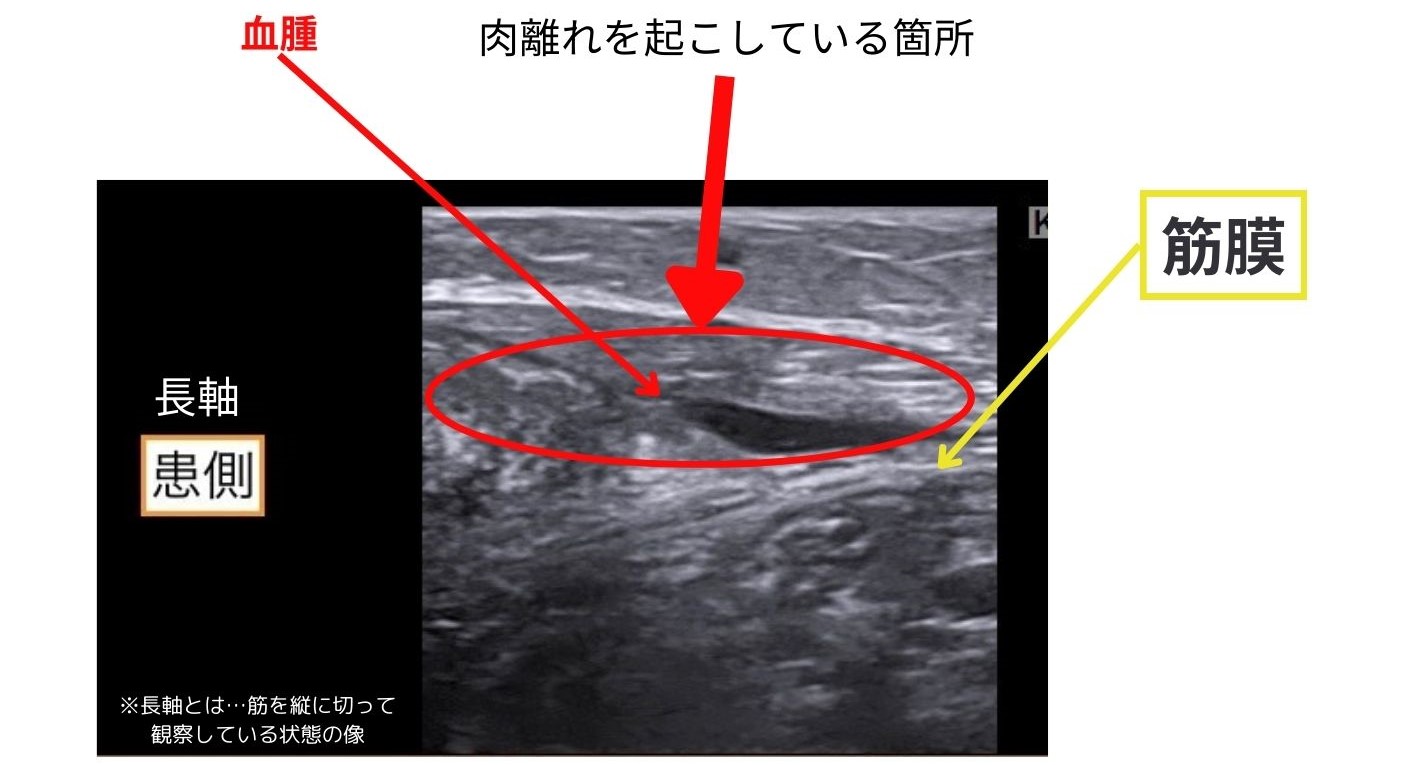

検査方法と重症度の見極め方(超音波・MRI)

来院時には、痛みの出る動作や押したときの反応などをもとに、現在の状態を確認する触診が行われることが多いと言われています。必要に応じて、エコーなどで筋肉の状態を確認するケースもあるようです。